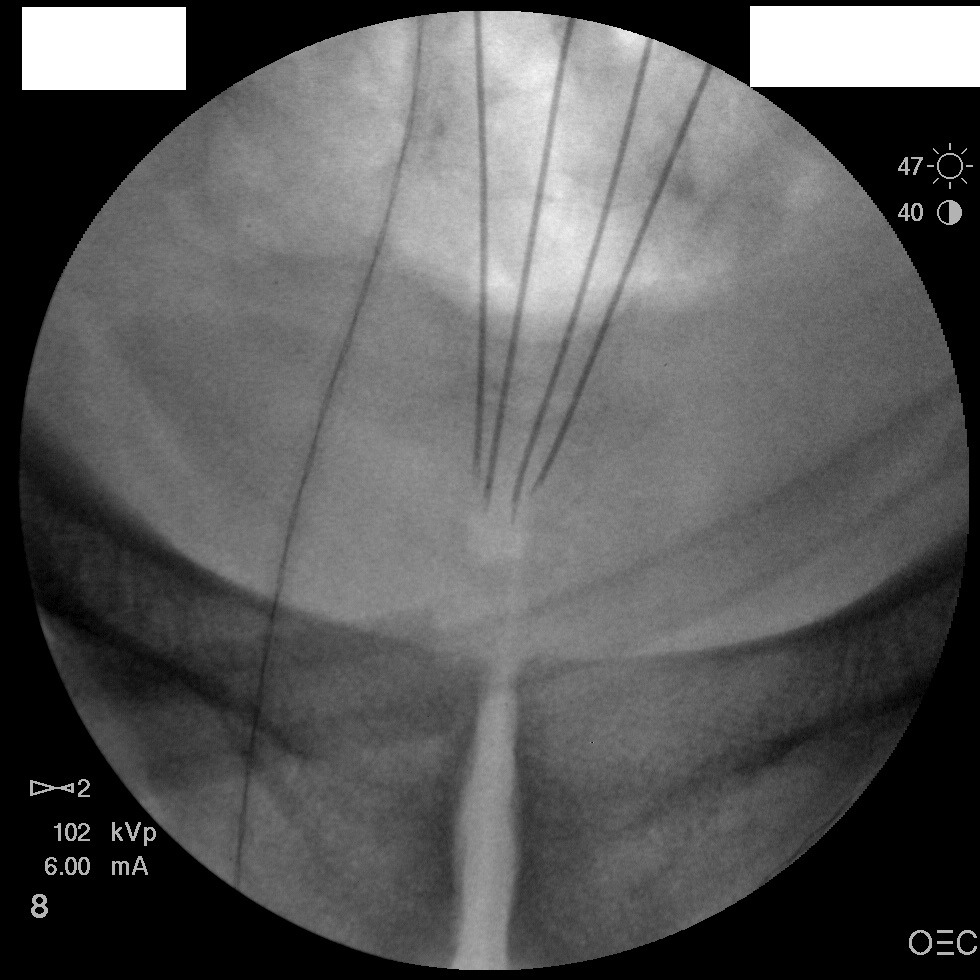

I have a patient with several months of coccyx pain. Worse with sitting, TTP over coccyx. Otherwise normal exam. No trauma, but she has an anteriorly displaced coccyx. Failed NSAIDs and no one around me does good pelvic floor PT. I scheduled her for ganglion impar injection, but her insurance won't pay for it. They wouldn't even let me to a peer-to-peer... they just straight up said they won't cover it. Any other treatment options? I don't want to send her to a surgeon. Thanks.